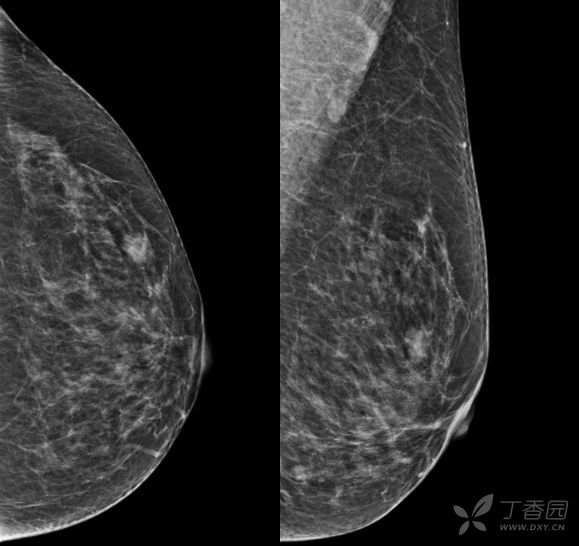

乳腺X线摄影

乳腺X线:左乳外上象限可见肿块,形态尚规则,边缘可见分叶,范围约12mm × 10mm。

因肿块边缘不规则,内部强化不均匀, TIC曲线初始相呈快速强化,延迟期呈平台型;DWI呈高信号,ADC值较低,考虑左乳外上象限肿块恶性不除外,BIRADS 4类。